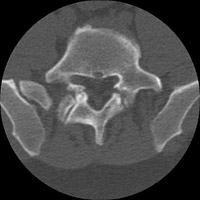

- Click on the image for a larger versionDAxial CT. This image confirms bilateral pars defects at L5-S1.